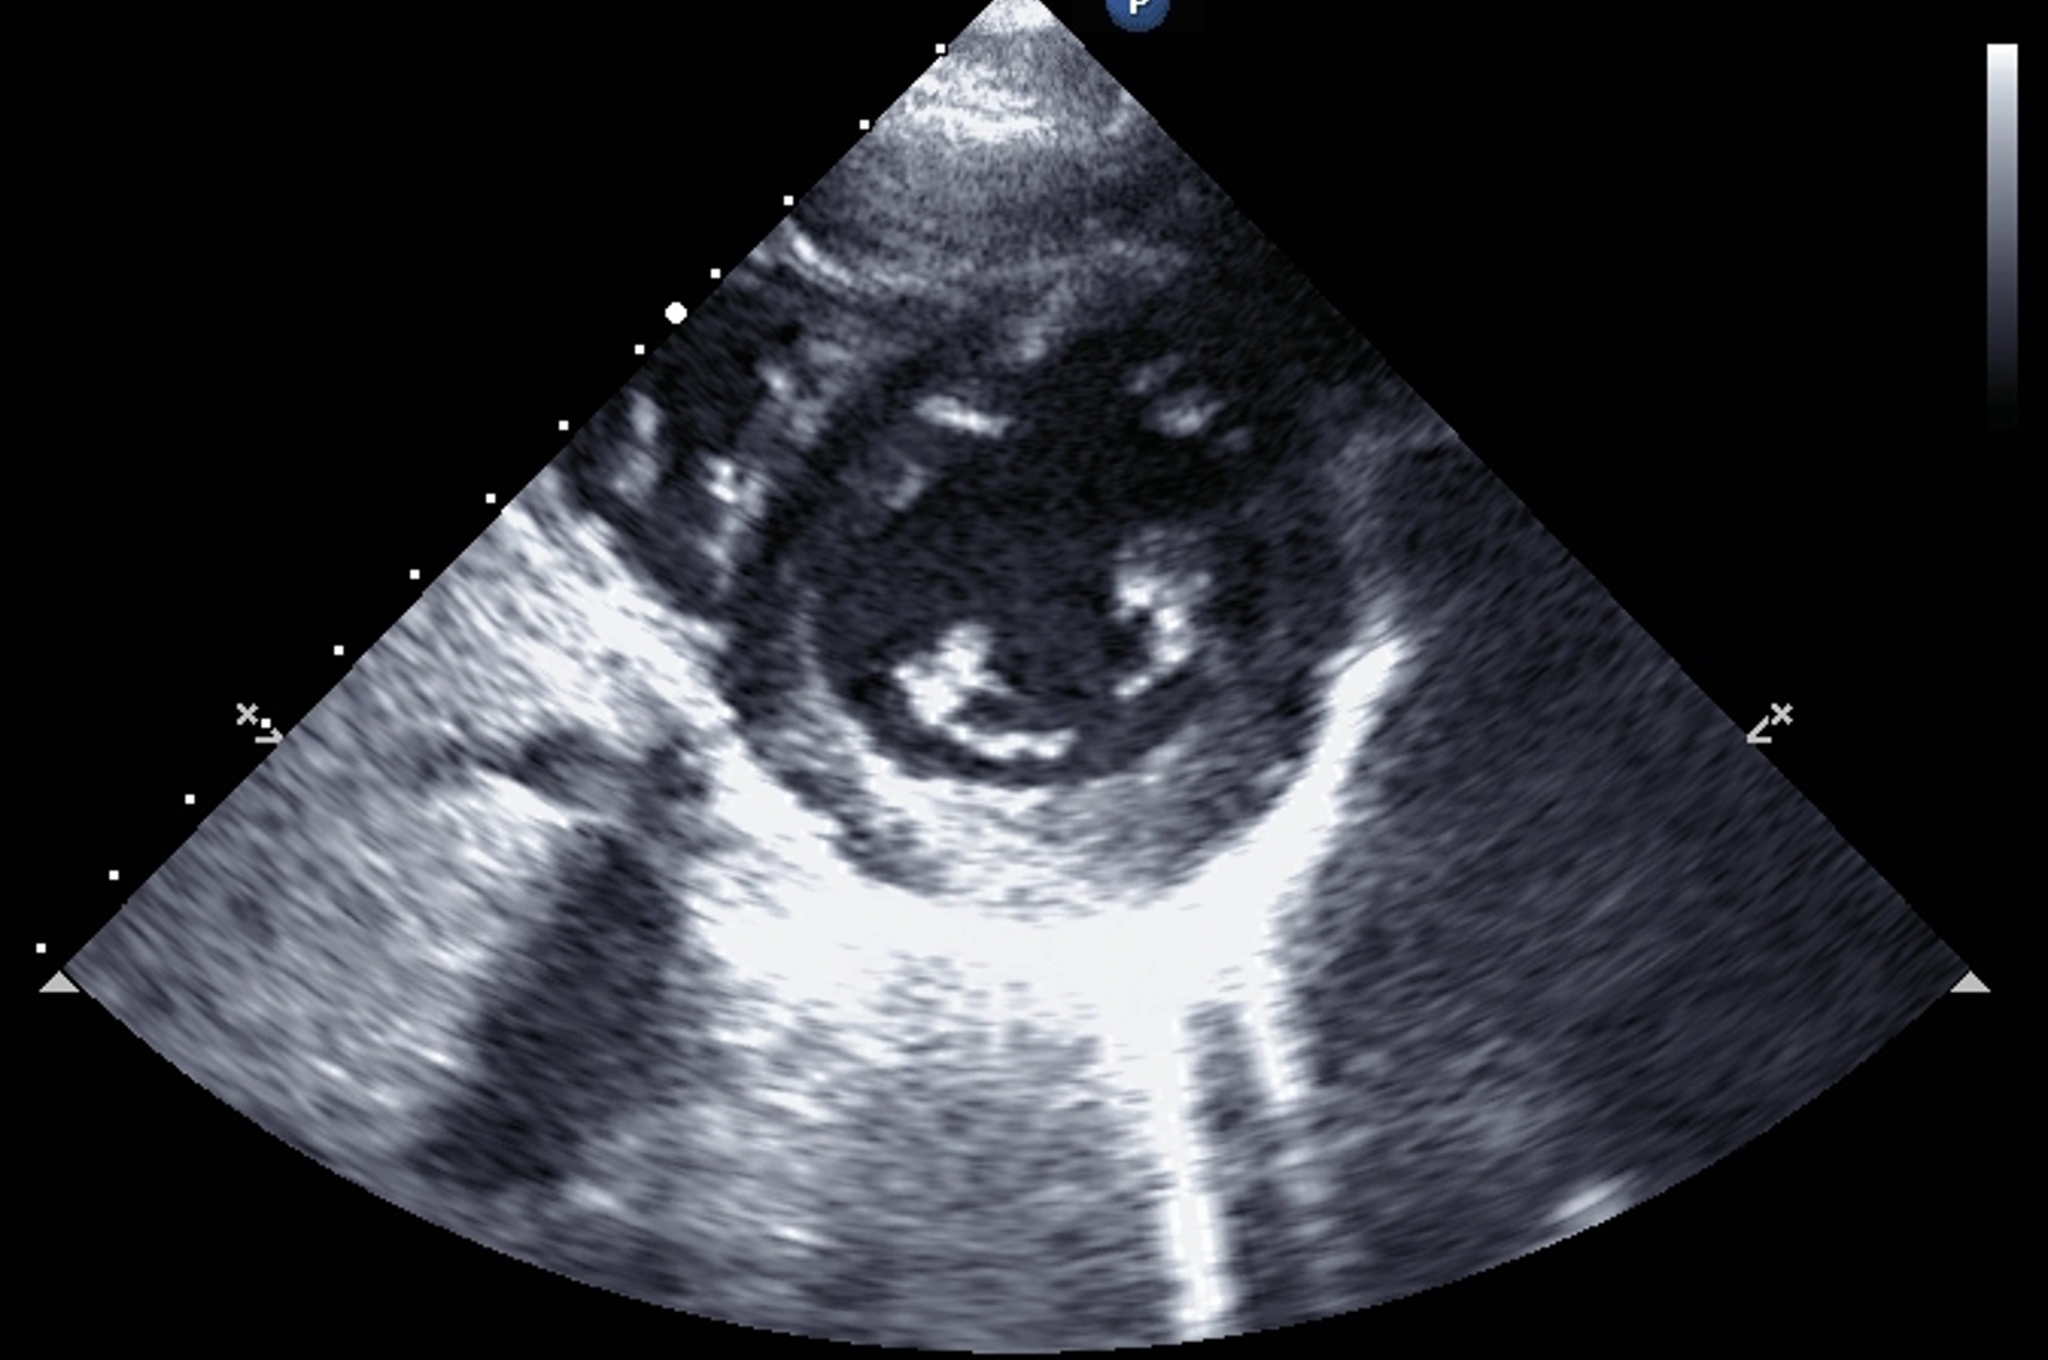

I forbindelse med revisjonen av studieplanen i medisin, Oslo 2014 (1), blir ultralyd en del av det organiserte undervisningsopplegget i flere fag. I en pilot ved Universitetet i Oslo har erfarne klinikere, sammen med lærere i basalfag, brukt ultralyd i gruppeundervisningen i anatomi i første studieår i medisinstudiet, som et tillegg til den tradisjonelle undervisningen. Hjertets struktur, leie og funksjon er blitt demonstrert på en ny og innovativ måte. Det er vist at bruk av ultralyd som et tillegg til ordinær undervisning, øker læringseffekten (2), men studenters forståelse av ultralydbildene har vært dårlig (3).